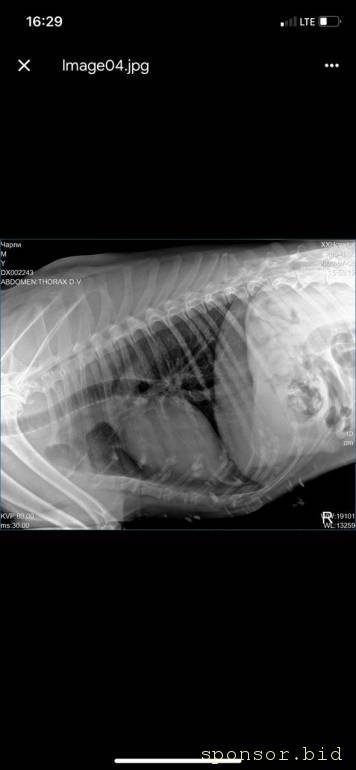

рентген

Помощь сбитой собачке - рентген 6.jpeg

Помощь сбитой собачке - рентген 1.jpeg

Помощь сбитой собачке - рентген 2.jpeg

Помощь сбитой собачке - рентген 3.jpeg

Помощь сбитой собачке - рентген 4.jpeg

Помощь сбитой собачке - рентген 5.jpeg

08.07.2022 г. передо мной на Варшавском шоссе сбили собаку, человек совершивший наезд даже не остановился и укатил дальше, я выбежала из машины, смогла остановить движение пары соседних полос, чтобы пес мог отползти на траву ( поднять и перенести не представлялось возможным, т.к. мне нельзя поднимать более 2 кг, более того непонятно что могла сделать собака в состоянии стресса и шока), после чего нашла парковку для машины и побежала к собаке, благо на тот момент несколько неравнодушных людей уже окружили его (это мальчик). Нами была вызвана полиция, составлено заявление ( но, думаем вряд ли кто-то будет этим заниматься.. так же сделан запрос в московскую службу видеофиксации, чтобы был сделан архив видео, если там есть камеры (тогда было не до этого, чтобы рассматривать есть ли они там), и в последствии приобщить к делу, или хотя бы найти того козла). Договорились со службой отлова, чтобы они на своей газели помогли довезти собаку до клиники шанс био, т.к. непонятно было что у нее с лапами, в клинике сделали рентген, несколько капельниц, обработали рану (т.к. задняя лапа разодрана до кости), взяли анализы, вкололи обезболивающие и отпустили.. т.к. у них нет стационара для бездомных, а так же хирурга, который мог бы сделать операцию. по заключению - кровоизлияние в глаз, открытая рана на левой заплюсне, вывих левого тбс (но вправить его нельзя, нужно делать операцию) порваны связки. по сумме в клинике оставили 14 500 руб. далее собаку отвезли в стационар надежда, с пятницы по воскресенье - обошлось в 10 552 руб (сам стационар, плюс лекарства, уколы и обработка ран, консервы, но он не ел). сегодня собаку возили на консультацию к хирургу в клинику беланта, было сделано дополнительно узи, на данный момент необходимо стабилизировать собаку, т.к. она еще в состоянии шока и с пятницы даже не ела, сейчас его опять повезли в стационар, необходимо еще делать уколы и обрабатывать рану, так же необходимо сделать 2 операции: на бедро (27200) и колено(55000), чтобы он смог передвигаться. в клинике заплатили 8167 с учетом лекарств. завтра планируется прием е еще одному хирургу в добрые руки, там по телефону озвучили цены на операции ниже чем в беланте, но нужен осмотр хирурга и его заключение. итого на данный момент на собачку ушло 33 219 руб. просим в сложившейся ситуации финансово помочь в судьбе пса, возможно найти ему любящих хозяев, на улицу его выкинуть уже просто невозможно, он там погибнет.. пес безумно умный, терпеливый, добрый, за все время ни разу не пытался агрессировать, укусить или что-то еще..